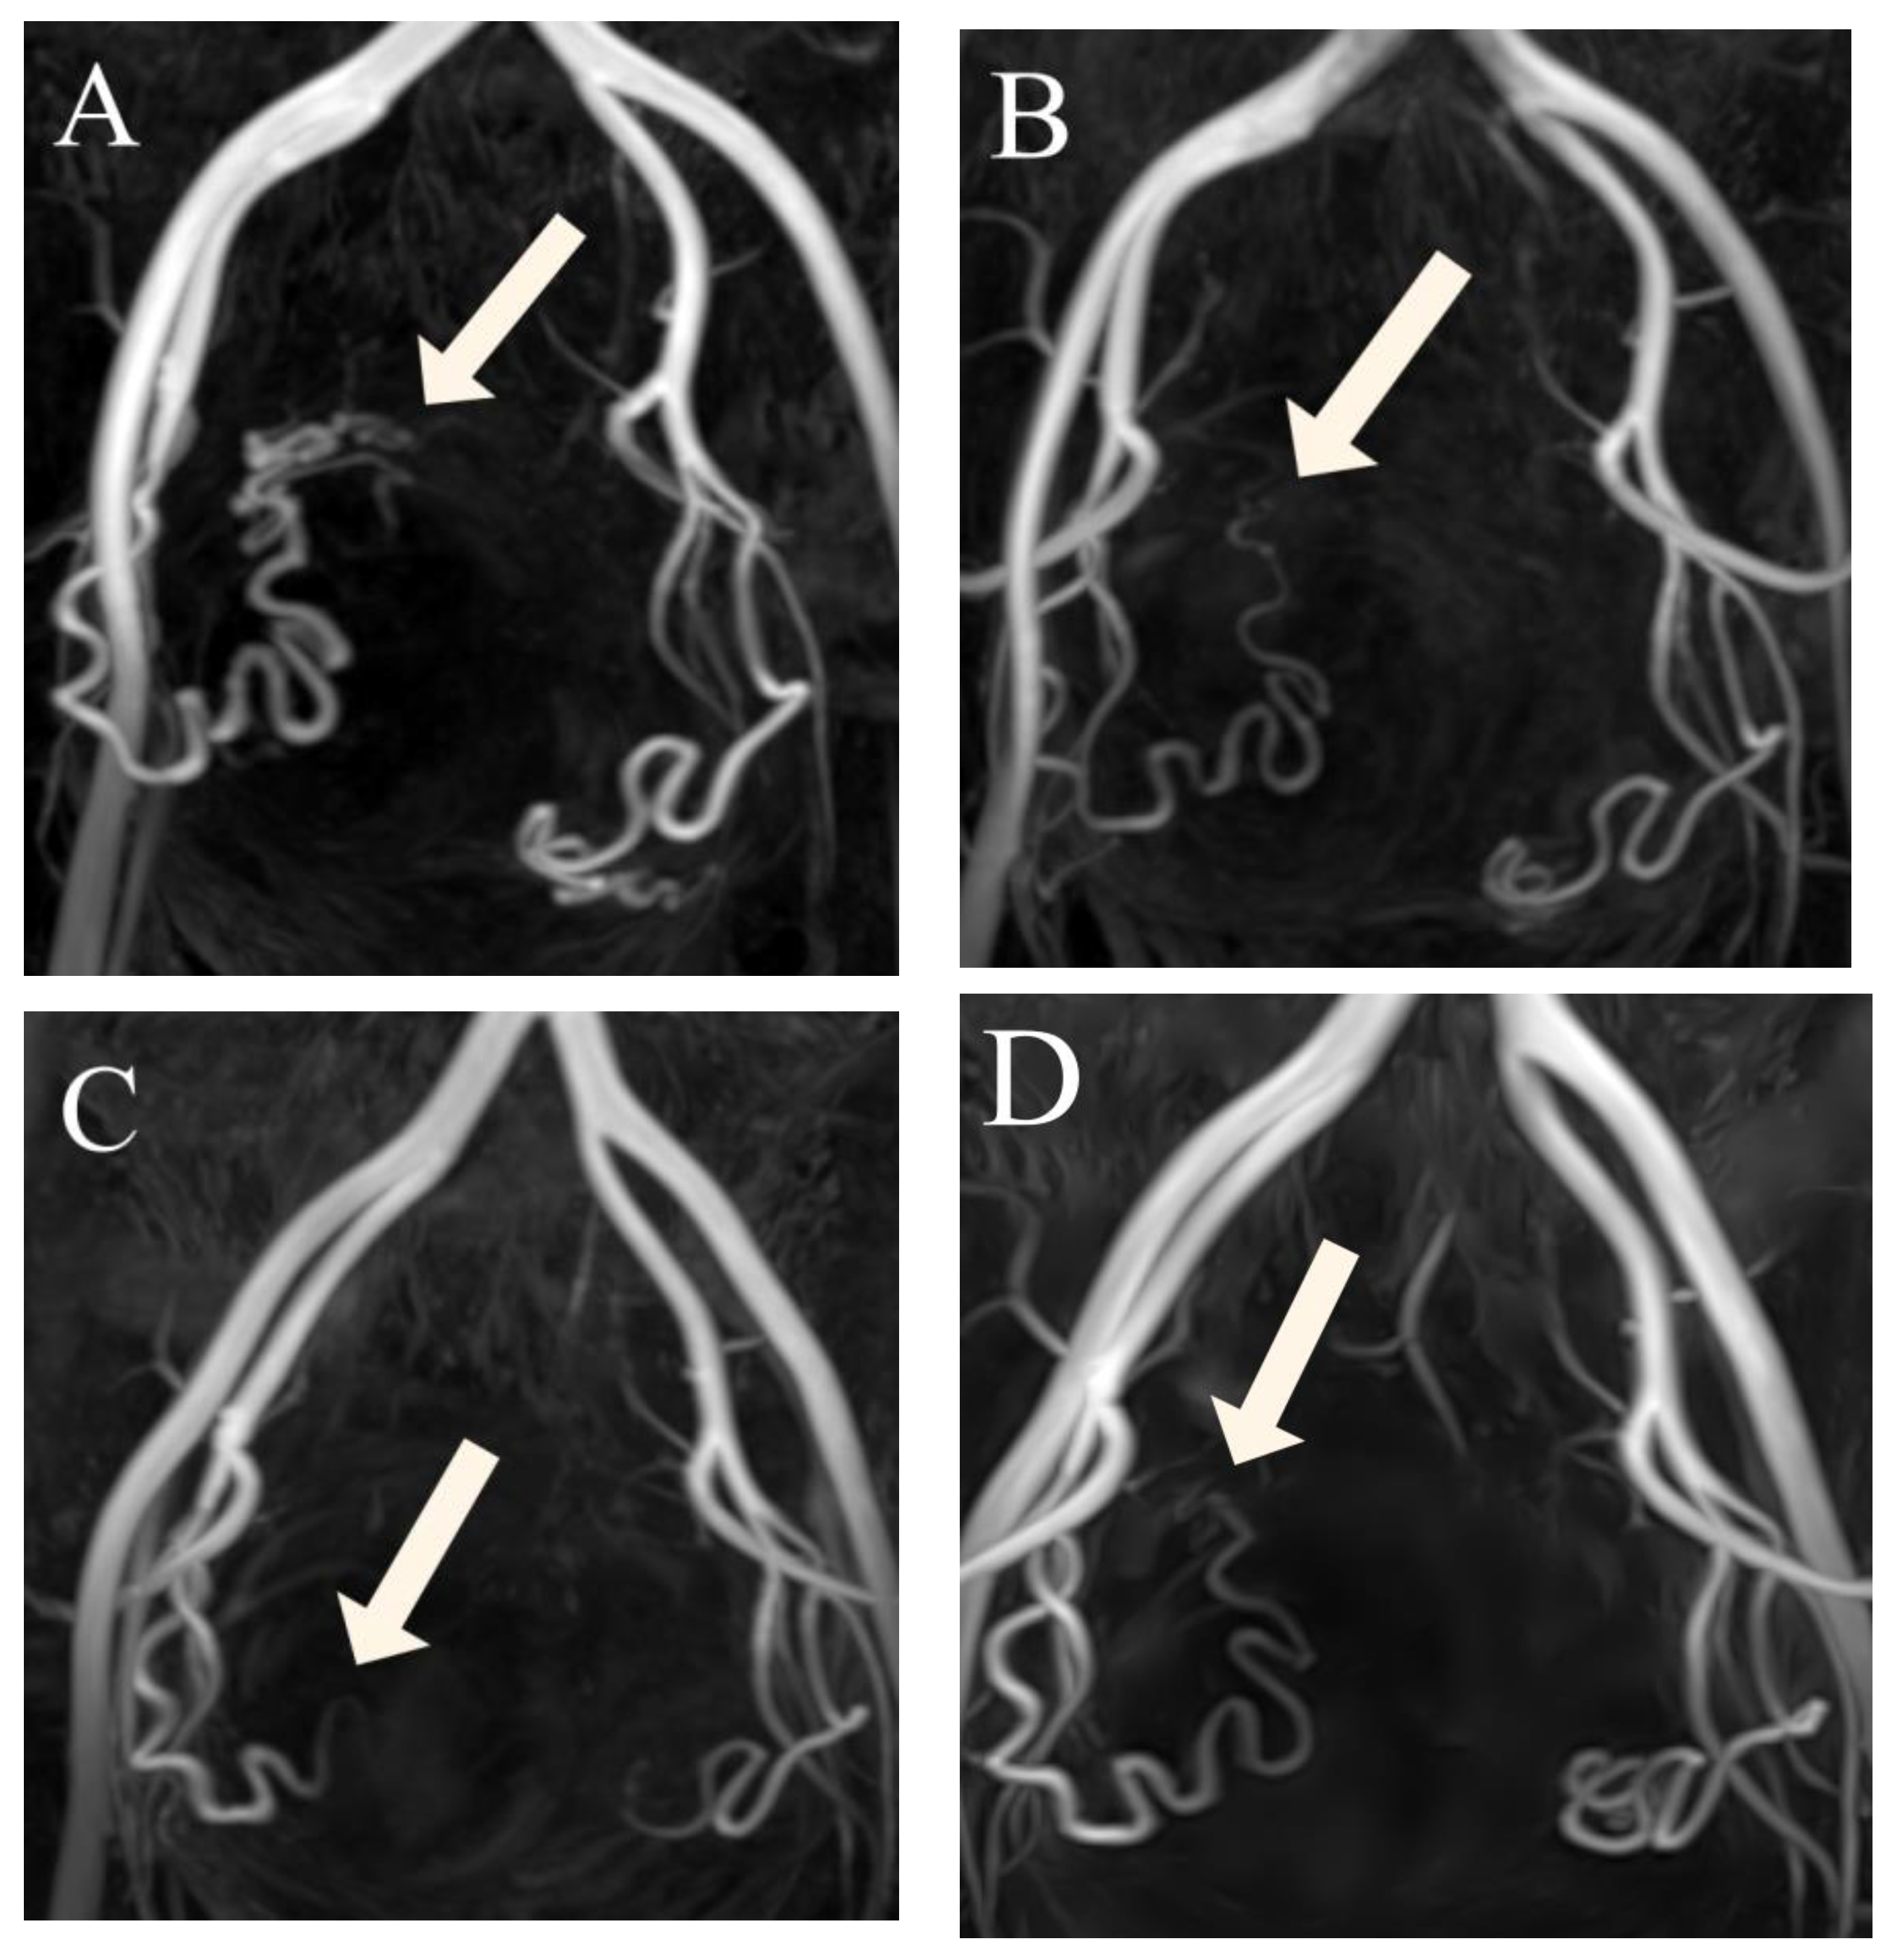

Figure 3.

(A–D) Three-dimensional non-contrast-enhanced magnetic resonance angiography image from a 49-year-old woman, suggesting luminal recanalization of the uterine arteries after uterine artery embolization. (A) Before uterine artery embolization: visualization of the right UA (arrow) forming the peritumoral plexus (score 4). (B) Three months after uterine artery embolization: visualization of the right uterine artery (arrow) until the ascending segment (score 3). (C) Six months after uterine artery embolization: visualization of right uterine artery (arrow) until the transverse segment (score 2). (D) Twelve months after uterine artery embolization: visualization of the right uterine artery (arrow) until the ascending segment (score 3).